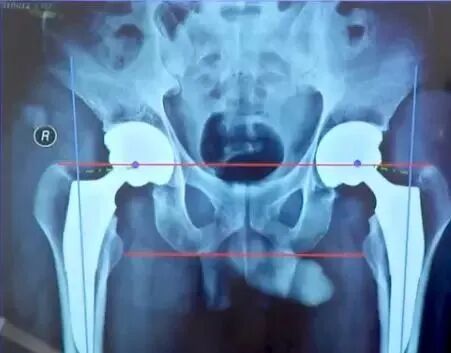

①肢体长度:真实长度(髂前上棘到内踝长度);

②影像学长度(耻骨下沿连线通过双侧股骨同一高度)

③髋臼角度:外展角在35°-45°之间前倾角在15°-20°之间;

④髋臼位置:恰好贴近泪滴外绿的外侧,日杯缘应位于髋臼内外侧壁之间;

肢体长度:

真实长度(髂前上棘到内踝长度)测量即可;

影像学长度(耻骨下沿连线通过双侧股骨同一高度),有些患者可能影像学上看着不等长,这时候考虑是处于外旋位,摆到正常内旋位即可准确判断是否等长。